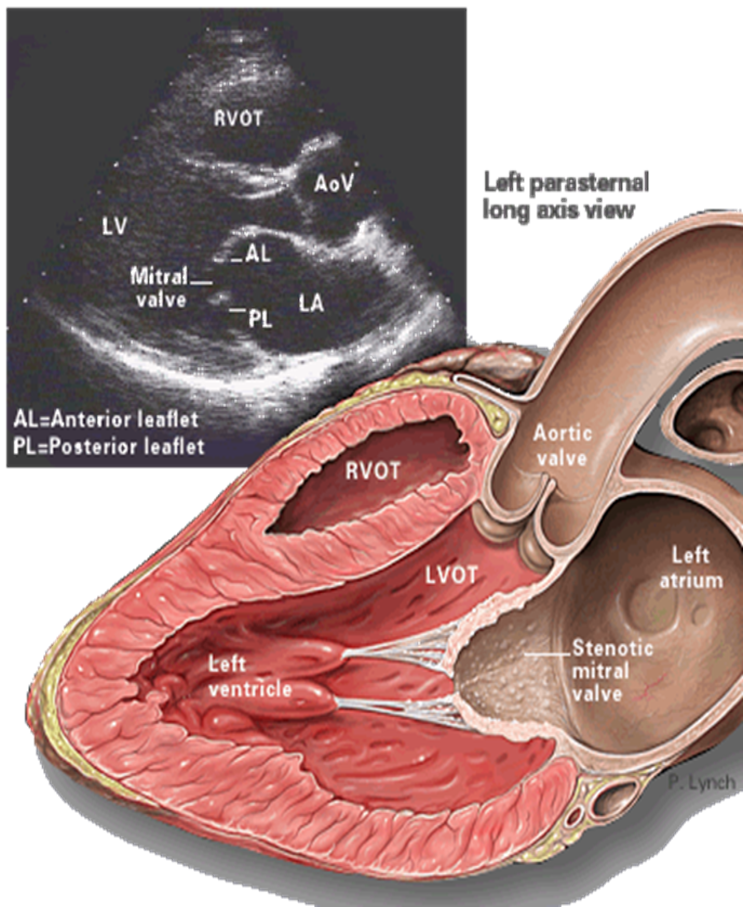

- TTE (Transthoracic echocardiography): best initial test to evaluate the mitral valve and quantify the anatomical extent of the stenosis.

Findings-

Reduced mitral valve area (MVA): ≤ 1.5 cm² (severe)

-

Thickened, calcified leaflets with commissural fusion

Increased mean diastolic pressure gradient across the mitral valve

RV dilation

LA enlargement

Evidence of pulmonary hypertension

Mitral stenosis refers to narrowing of the mitral valve orifice that occurs as a result of fusion of the leaflet commissures.